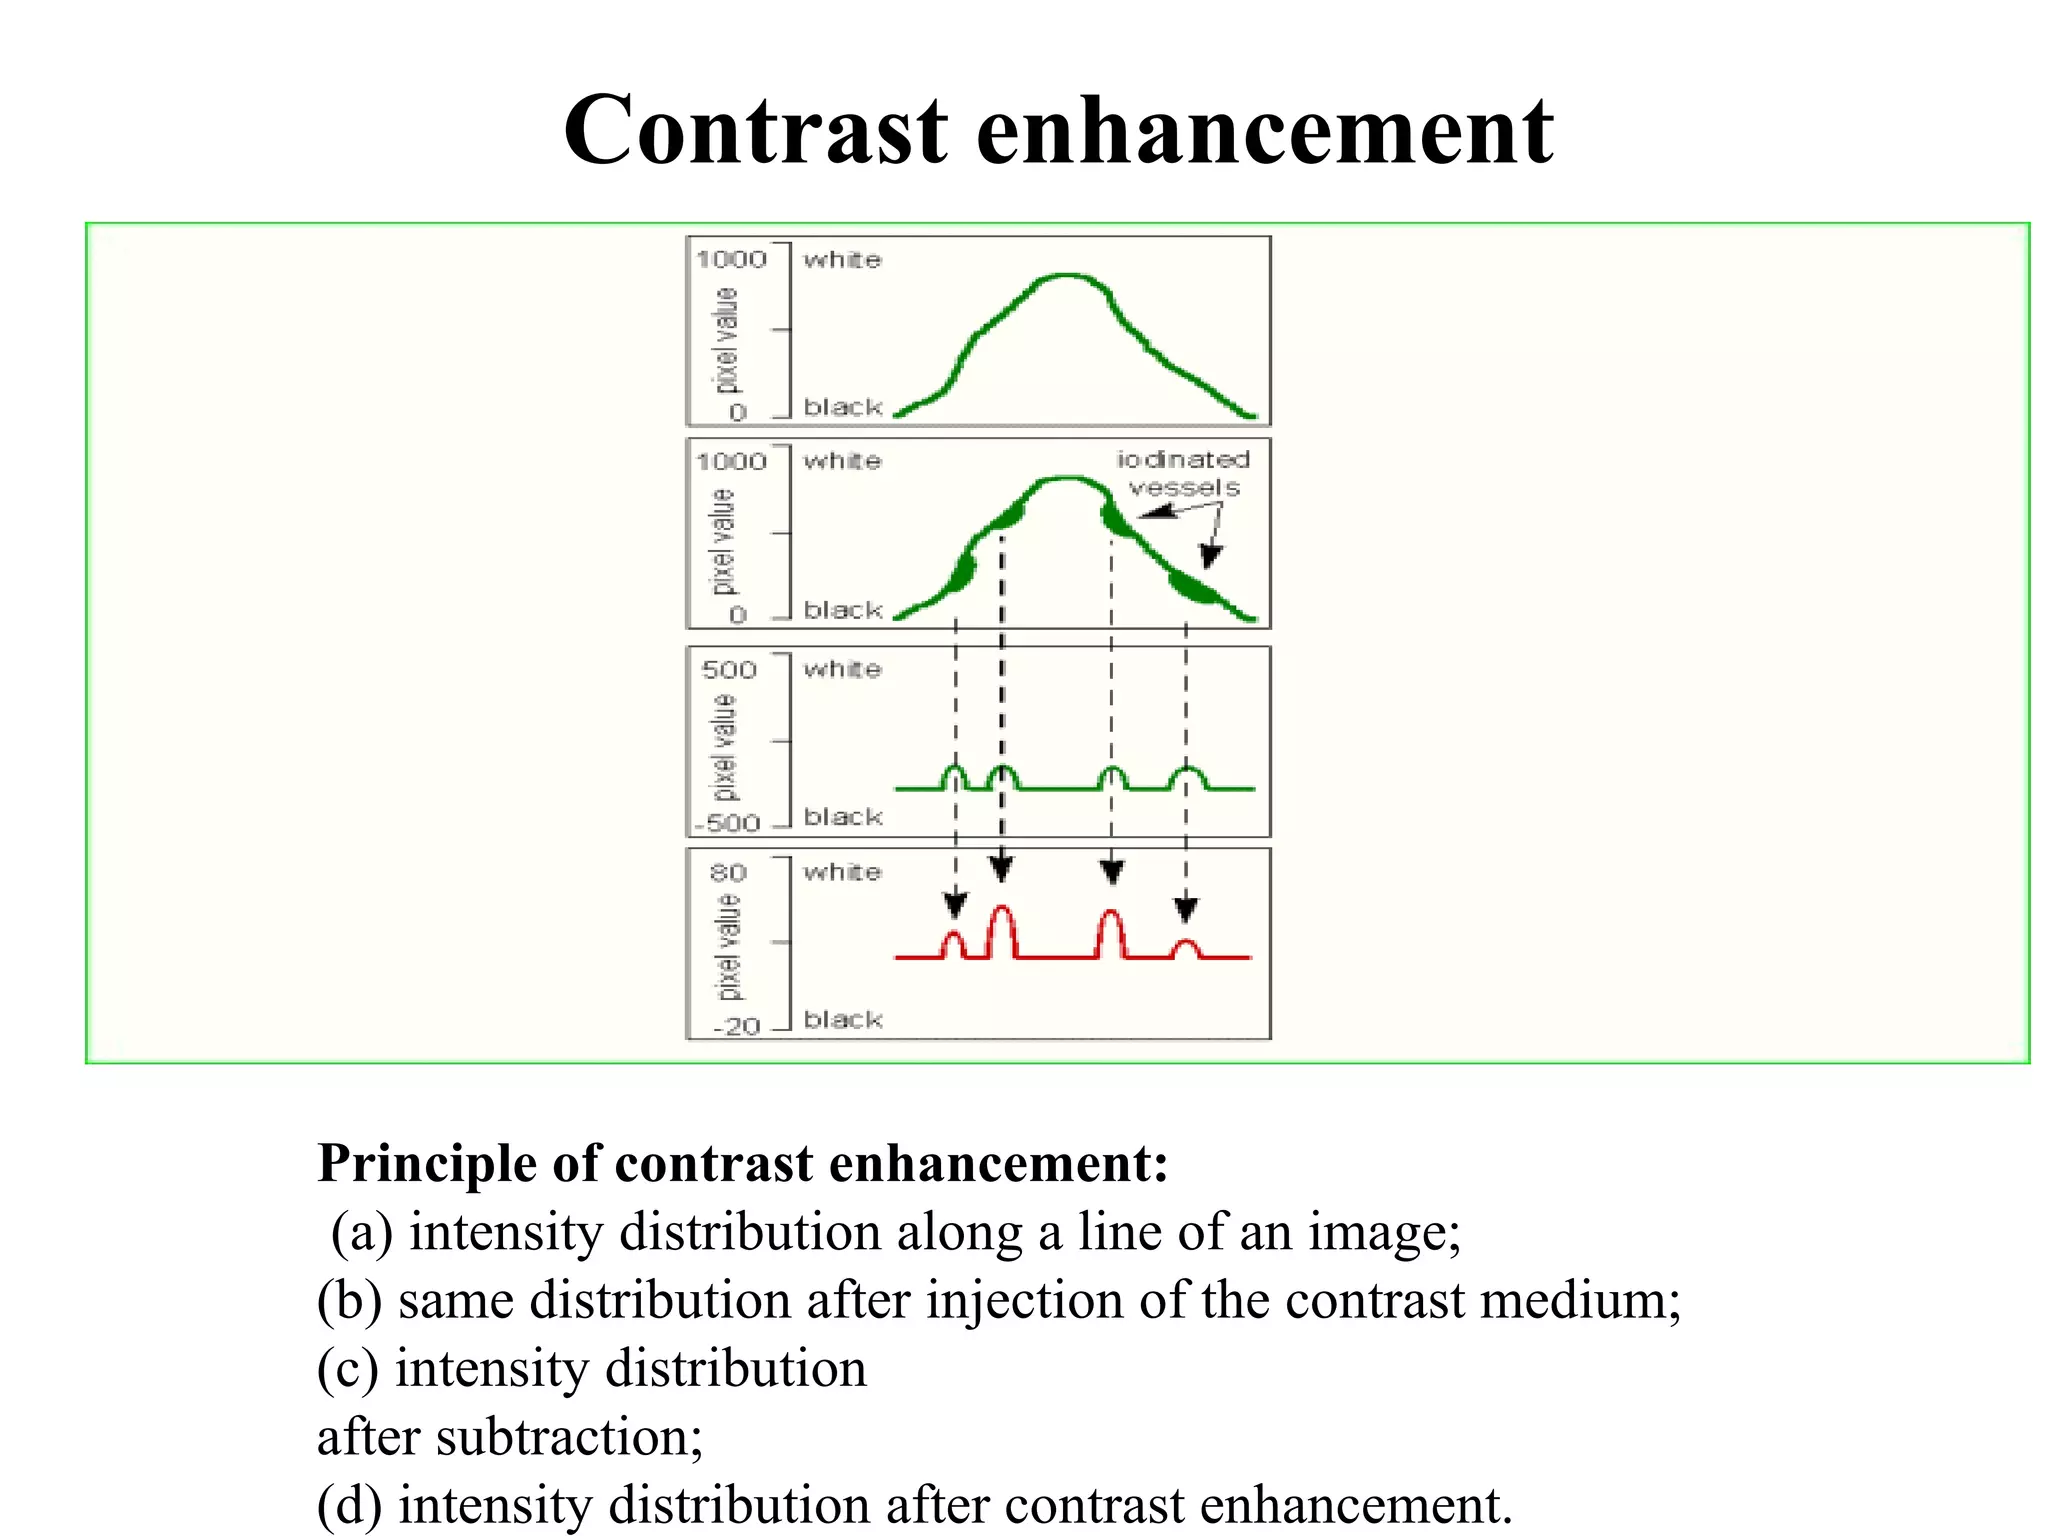

The document discusses various medical imaging modalities including x-rays, computed tomography (CT), and digital mammography. It describes the basic principles and historical development of these technologies, how images are formed, and what types of anatomical features and abnormalities they can detect. Key advances include the development of digital systems that allow image manipulation and remote consultation. While promising, digital mammography still faces challenges around resolution and cost.